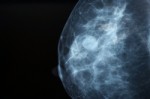

Find out about mammograms and what breast screening is all about. This article also explains who should be having mammograms in New Zealand today.